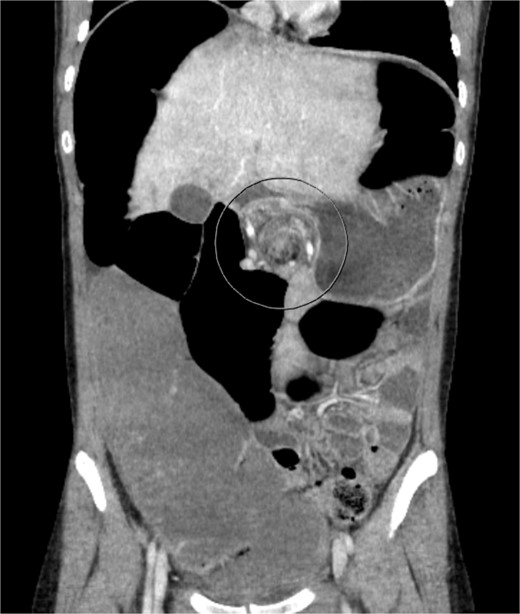

A 19-year-old female presented to the emergency department with complaints of epigastric abdominal pain, nausea, vomiting, and having passed no gas or bowel movements for 4 days. Her past medical history consisted of irritable bowel syndrome, gastroparesis, depression and anxiety, eosinophilic esophagitis, and opioid abuse. She did not take any medication for her depression and anxiety. Her past surgical history included upper and lower endoscopy and surgical ablation of genital warts. She has a significant family history of a brother who has ulcerative colitis. Upon physical exam, her abdomen was tympanic and distended. There was epigastric tenderness with no guarding or rebound tenderness. Due to concern for a bowel obstruction, a nasogastric tube was placed, and a computed tomography (CT) scan was done (Fig. 1). Imaging showed immense distension of the colon due volvulus at the splenic flexure with narrowing of the mesenteric vasculature and free fluid in the abdomen. The patient was taken for an exploratory laparotomy emergently with a preoperative diagnosis of a large bowel obstruction due to internal hernia versus volvulus. During the operation, it was found that the distal transverse colon was the point of obstruction and showed scarring with dilatation proximal to the narrowing, and there was no internal hernia identified. An extended right colectomy was performed with ileocolic anastomosis. She had a return of bowel function on postoperative Day 4. Six days post-operation, the patient began to have nausea and vomiting and had not had a bowel movement in 2 days. Eight days post-operation, a CT scan was performed that illustrated proximal small bowel dilatation (Fig. 2). With concerns of another bowel obstruction, an exploratory laparotomy was performed. During the operation, a dilated small bowel and a twisted sigmoid colon were found consistent with a large bowel obstruction secondary to sigmoid volvulus. A completion colectomy with end ileostomy was performed.

CT of the abdomen performed 8 days post operation. Shows proximal dilatation of the small bowel.